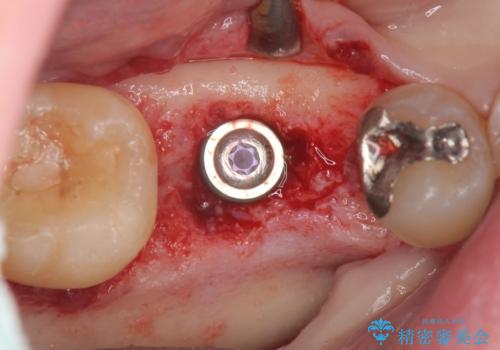

抜歯後は、前後の歯を削らずにしっかりと咬合力を回復できるインプラント治療を選択されました。

虫歯の放置により吸収してしまった骨も造成を行うことでインプラント周囲環境をしっかりと整えています。